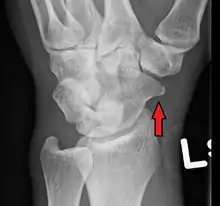

![]() | |

| An X-ray showing a fracture through the waist of the scaphoid | |